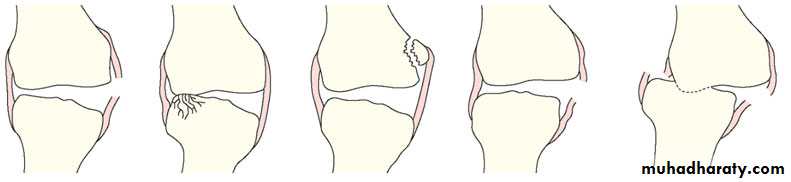

SALTER-HARRIS classification into:

Type1; the fracture pass through the Epiphysial plate only and there is no displacement.

Type 2; fr line pass through most of the epiphysis and cuts partly on the metaphysis displacing the epiphysis and the attached small metapliyesial triangular segment.

Type 3; partial epiphysial plate fracture that will continue through the epiphysis separating epiphysial fragment.

Type 4; the fracture line cuts through the epiphysis and the metaphysis separating an epiphysial fragment with its opposed epiphysial plate and metaphysis.

Type 5; its compression fr of the epiphysis that does not usually seen in x-ray. It carries the worst prognosis, as it’s commonly lead to growth disturbances.

Type 1 and 2 are commoner and carry good prognosis, while type 3 and 4 are less common and carry poorer prognosis.